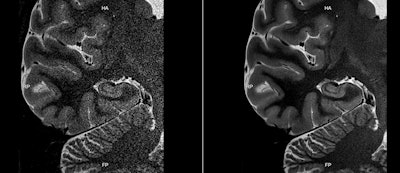

Finally, Aquilion One / Prism uses Canon's Advanced Intelligent Clear IQ Engine (AiCE), a deep learning-based protocol for reconstructing CT images that distinguishes signal from noise to produce sharper images at lower radiation dose. AiCE works on a variety of images, including brain, lung, cardiac, and musculoskeletal. AiCE for Aquilion One / Prism is awaiting U.S. Food and Drug Administration (FDA) 510(k) clearance; the new edition itself has received 510(k) clearance.

Canon debuted AiCE at RSNA 2018 as a data reconstruction tool for the Aquilion Precision high-end CT scanner. At this year's meeting, the company is demonstrating AiCE for a broader range of products and clinical applications, all the way down to the company's workhorse Prime SP scanner.

Canon currently has 510(k) clearance for AiCE for chest, abdomen, and pelvis applications on Aquilion Precision; it is applying for regulatory approval for neuro, cardiac, and musculoskeletal use.

At RSNA 2018, Canon launched its AiCE deep learning-based reconstruction technology for CT, and at RSNA 2019, the company is migrating AiCE to its MRI line -- specifically, the Vantage Orian 1.5-tesla and Vantage Galan 3-tesla scanners.

AiCE for MRI was developed by first training the algorithm on high-quality data with a high signal-to-noise ratio. The company then fed different levels of Gaussian noise into the images and trained AiCE to sense the difference between signal and noise to develop images that match the original high-quality data.

AiCE can help users by accelerating MR scanning, improving image quality, or increasing the image matrix -- or a combination of all three. Canon submitted its application for 510(k) clearance of AiCE for MRI several months ago.